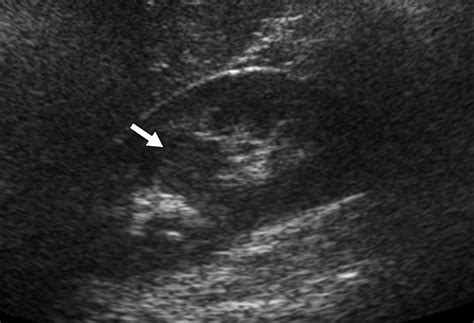

• hypertrophied column of bertin radiology

• prominent column of bertin kidney

• hypertrophied column of bertin

• column of bertin hypertrophy

• column of bertin kidney